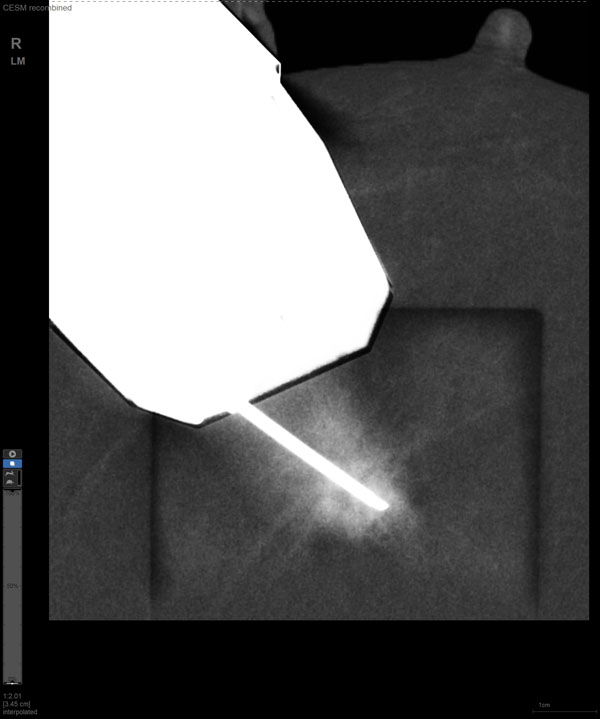

某患者增强磁共振成像MRI显示肿瘤周边有活性,中心区域有组织坏死。为得到准确的病理结果,穿刺靶区需避开肿物坏死区域。在与患者主管医生充分讨论后,放射科医生为患者行CEM引导下穿刺活检术。术中,CEM检查肿物同样显示为环形强化,巧妙避开坏死区域后,穿刺靶区选择了肿物增强早期明显强化区域,术程顺利,仅用时15分钟。术后该患者病理结果为浸润性导管癌Ⅱ级。

CEM引导下穿刺